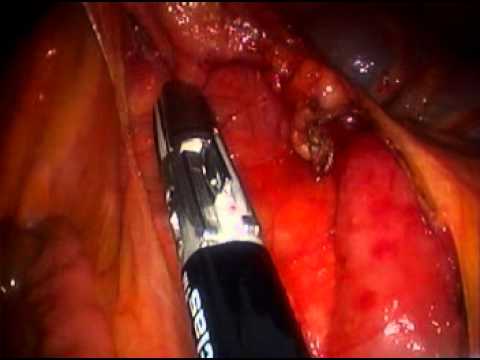

Hemikolektomia laparoskopowa prawostronna

Film medyczny śródoperacyjny przedstawiający zabieg hemikolektomii laparoskopowej prawostronnej u 60-letniego pacjenta z rakiem zagięcia wątrobowego okrężnicy.